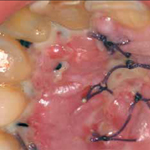

CHIRURGIA PARODONTALE

La parodontologia si occupa delle diagnosi e della terapia delle malattie (malattie parodontali o parodontopatie, o piorrea ) che interessano l'insieme dei tessuti che concorrono a formare l'organo di sostegno del dente.

Quando queste malattie diventano piu' gravi si consiglia di intervenire con la chirurgia parodontale, che ha come obiettivo l'eliminazione delle tasche gengivali ed ossee, la levigatura delle radici e il curettage sotto controllo visivo diretto. Questo avviene attraverso metodiche rivoluzionarie che servono non solo a fermare la malattia parodontale, ma anche a rigenerare e ricostruire il tessuto perduto.

Nel nostro studio, per risolvere le recessioni gengivali, si effettua sia la chirurgia plastica gengivale che la chirurgia estetica gengivale.

PRGF

La Tecnologia PRGF (Plasma Rich in Growth Factors) e' il sistema autologo piu' avanzato di Plasma Ricco in Piastrine. Si basa sull'attivazione delle piastrine del paziente stesso per la stimolazione e l'accelerazione della rigenerazione dei tessuti.

E' la prima tecnica studiata specificamente per la terapia odontoiatrica. La sua efficacia e' confermata da piu' di 10.000 pazienti trattati nelle differenti specialita' mediche.

Tecnicamente si tratta di un autoinnesto, poiche' sono le proteine proprie del paziente ad innescare e accellerare i processi riparativi e la conseguente rigenerazione dei tessuti; e' particolarmente utile oltre che indicata per i pazienti con problemi di cicatrizzazione o di scadente attecchimento delle rigenerazioni ossee, come nel caso dei forti fumatori o diabetici.